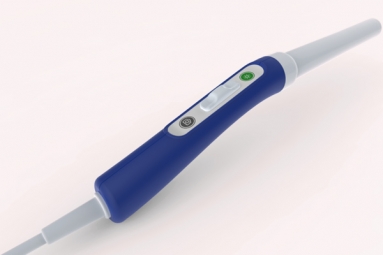

Read MoreIndian-American Scientist Builds Inexpensive Tool to Spot Cervical Cancer December 21, 2018 09:32

An Indian-American Professor of Global Health and Director of Global Women's Health Technologies at Duke University, Dr. Nimmi Ramanujam, has developed a low-cost diagnostic device called the 'Pocket Colposcope' to detect cervical cancer. According to…